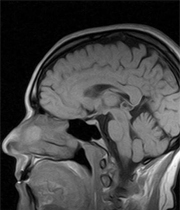

Los genes son responsables del 40 por ciento de la inteligencia a lo largo de la vida del ser humano, mientras el otro 60 por ciento está determinado por el contexto, según un estudio genético divulgado este jueves en Australia.

El experto australiano, junto a investigadores escoceses y británicos, examinó los test de inteligencia de unas 2.000 personas realizados en Escocia cuando tenían 11 años de edad y posteriormente de estas mismas personas con una edad superior a 65 años para entender por qué algunas inteligencias envejecen mejor que otras.

Durante el estudio, los expertos también tomaron muestras genéticas y cuantificaron el papel de los genes en los cambios de la inteligencia a medida que el ser humano envejece.

"Calculamos que entre un cuarto y un tercio de estos cambios son genéticos", indicó Visscher, quien defendió la importancia de estos estudios de los genes para identificar factores implicados en el deterioro mental de los ancianos, lo que podría ayudar a entender mejor enfermedades como el Alzheimer.